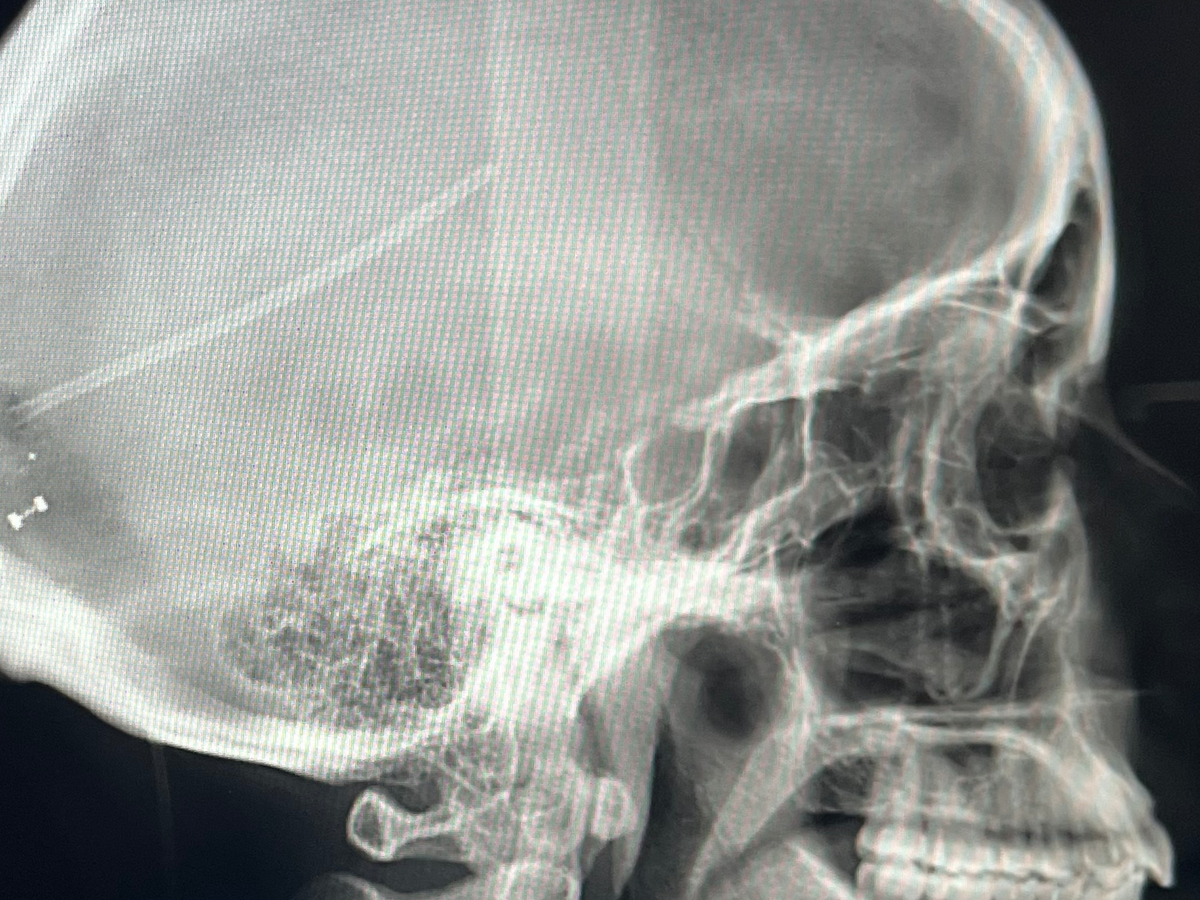

I went to Urgent Care for a CAT scan and from there, was rushed to the ICU. After MRIs, we discovered that the cerebral fluid in my brain wasn’t draining due to a pinched occipital ventricle, and the built up fluid was pushing on my eyes. This was not a problem that a lumbar puncture could fix, it required a CSF Shunt / VP Shunt. This meant that a tube would be inserted into my brain and connected to a valve attached to my skull. From there, a second tube would stretch under my skin from the valve in my skull all the way down to my stomach, acting as a drainage system for any excess fluid. So technically it was brain & abdominal surgery. People ask me when the shunt will be removed but these tools that are foreign to my body are here to stay, this isn't something that gets taken out after X amount of months. If I’m lucky, they’ll keep functioning well and future surgeries won't be necessary.